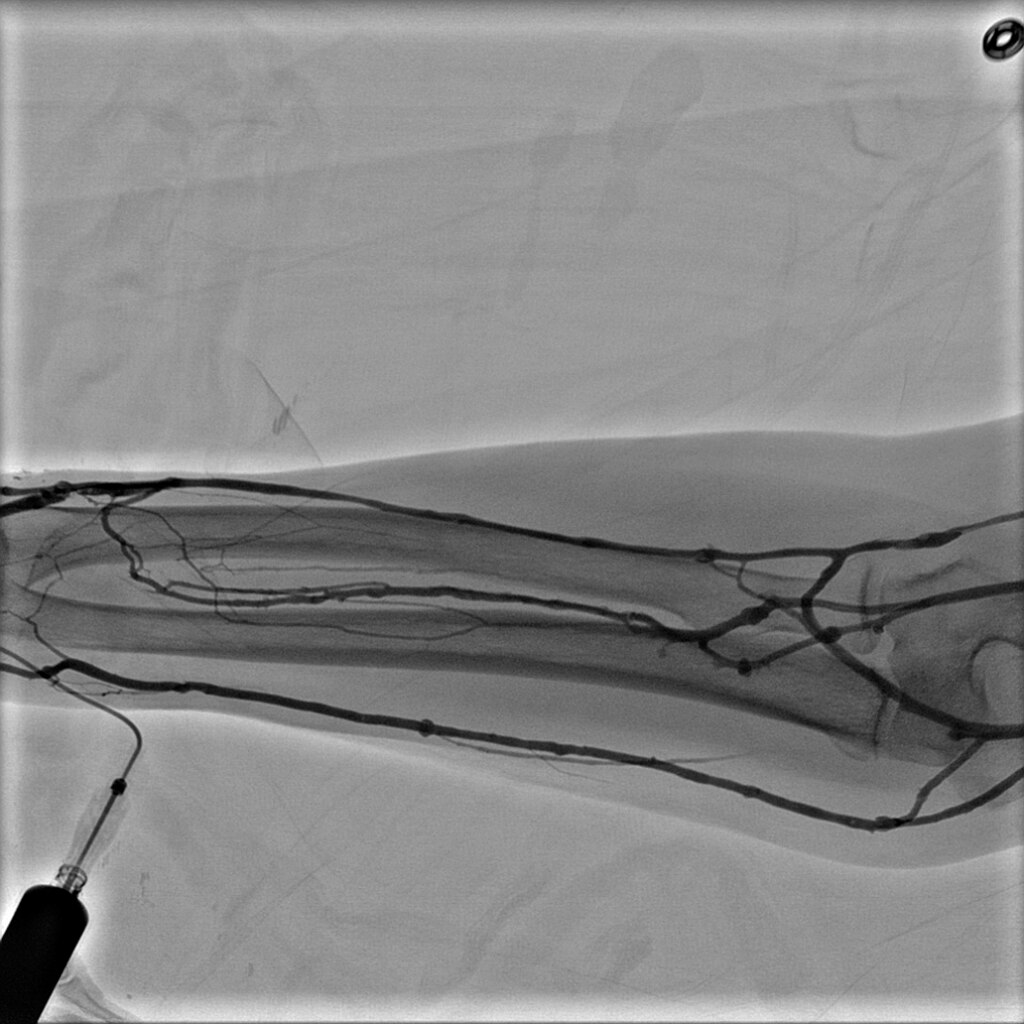

- Innova Breeze — простой и автоматизированный способ болюсного исследования. Модуль Innova Breeze для получения субтракционного периферического изображения с целью отслеживания контрастного вещества в реальном времени с возможностью изменения скорости перемещения стола. Возможен захват обеих конечностей одновременно с высоким разрешением сосудов малого диаметра. Независимый сдвиг пикселей позволяет сдвигать маску изображения обеих ног по отдельности, чтобы выровнять любые несовпадения.